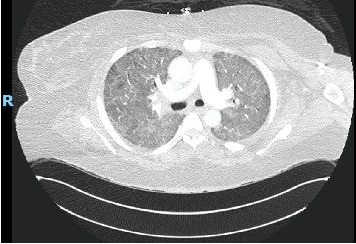

Background: Diffuse alveolar hemorrhage (DAH) is a potentially life-threatening condition which can present with hemoptysis, diffuse alveolar infiltrates, anemia, and hypoxic respiratory failure. Antisynthetase syndrome (AS) is a rare autoimmune disorder most often characterized by nonerosive arthritis, proximal muscle weakness with elevated muscle enzymes, Raynaud's phenomenon, hyperkeratosis of the digits (mechanic's hands), and interstitial lung disease. According to large population studies, AS has an annual incidence of 0.56 per 100,000 persons and prevalence of 9 per 100,000. The most common autoantibody is anti-aminoacyl-transfer RNA synthetase for histidine (anti-Jo-1) with a reported prevalence of 20%-30%, whereas anti-Pl-7 (for threonine) accounts for less than 5% of all autoimmune myositis. Specific myositis autoantibodies determine clinical phenotype. PL-7 is characterized by interstitial lung disease, myositis, and arthritis. Autoimmune myositis, specifically AS, is a rare cause of DAH. Herein, we describe the first reported case of PL-7-associated AS with DAH. Case Presentation: A 41-year-old female presented with worsening shortness of breath and hemoptysis. Laboratory studies included a hemoglobin of 10.5 g/dL, mildly elevated liver enzymes, and a creatine phosphokinase (CPK) of nearly 4000 U/L. CT of the chest showed diffuse ground glass opacities bilaterally. Serial aliquots of the bronchoalveolar lavage (BAL) fluid revealed progressively hemorrhagic return and histopathologic analysis consistent with DAH. Other concurrent causes of DAH were ruled out. Conclusion: Although rare, AS should be considered a cause of DAH, particularly in patients presenting with symptoms of muscle weakness and arthritis or with evidence of mechanic's hands.

Abstract Image